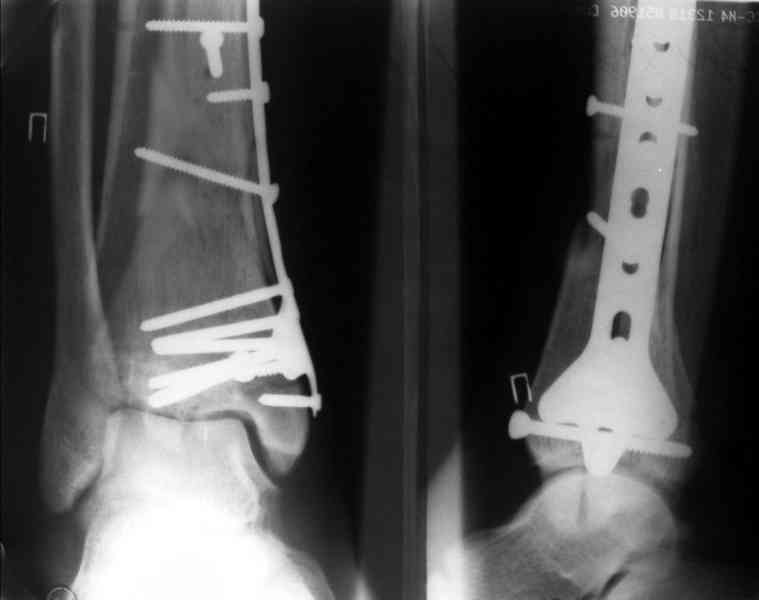

На рентгенограммах типичный перелом пилона по типу С-3. есть опыт до 100 открытых опреаций у нас в клинике. 20 примерно в год. Принцип один -все внутрисуставные переломы нуждаются в открытой репозиции и внутренней стабильной фиксации. При поступлении КТ не надо, так как получается только нагромождение костей. Истинной картины нет. Главное восстановить длину малоберцовой кости - это ключ к успеху. При поступлении меньше всего надо думать о сосудистых расстройствах, т.к. сама операция и репозиция даже сначала частичная даёт улучшение сосудитых нарушений. Причём очень быстро. Операция в 2этапа. При поступлении доступ позади наружной лодыжки, причём обязательно. После этого репозиция малоберцовой кости и фиксация пластиной 1/3 трубки под винт 3,5. Дренаж и любой аппарат наружной фиксации. Затем после спадения отёка на 5-7-10 день аппрат снимается и дугообразный разрез спереди от медиальной лодыжки 10-12 см. Главной чтобы расстояние между 1 и вторым разрезом было не меньше 7-8 см. Тогда не будет некрозов лоскутов. Таранная кость используется как матрица на неё укладываются отломки и фиксируются пицами. Ренг-контроль. Отломки лежат все отдельно, но ничего не высыпется. При переломах С-3 всегда нужна костная пластика (из крыла). Фиксация пластиной лист клевера простой или LCP. Гипс не нужен. Дренаж до 48 часов. Операция длится 3-4 часа обязательно без жгута. Посылаю примерно такой же случай.

Послала ещё два снимка, если не пройдут, пошлю ещё. Дрягин. Если есть вопросы, готов ответить.

Посылаю результат лечения предыдущего больного через год.